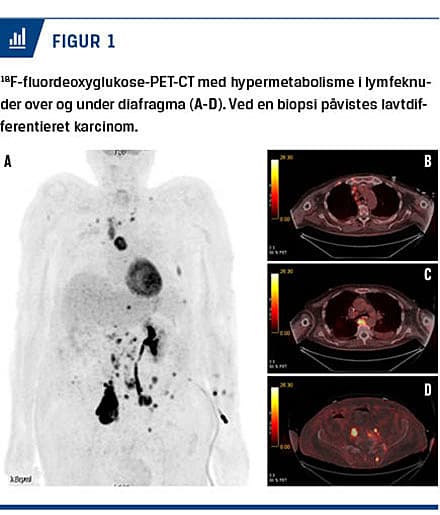

Ved analyse af CSV påvistes der GABABR-antistof-fer i høj titer, og man påbegyndte behandling med terapeutisk plasmaferese (fem gange over ti dage). Efter den anden plasmaferese var den kliniske tilstand i diskret bedring. Patienten åbnede øjnene på tiltale, men var fortsat svært konfus. En fluordeoxyglukose-PET-CT viste multiple lymfeknuder med øget metabolisk aktivitet over og under diafragma (Figur 1), og ved en lymfeknudebiopsi påviste man småcellet udifferentieret cancer. Cytostatisk behandling vurderedes ikke at være mulig pga. patientens almentilstand. Han var dog i cerebral bedring og kunne nu følge personalet med øjnene og genkende pårørende.